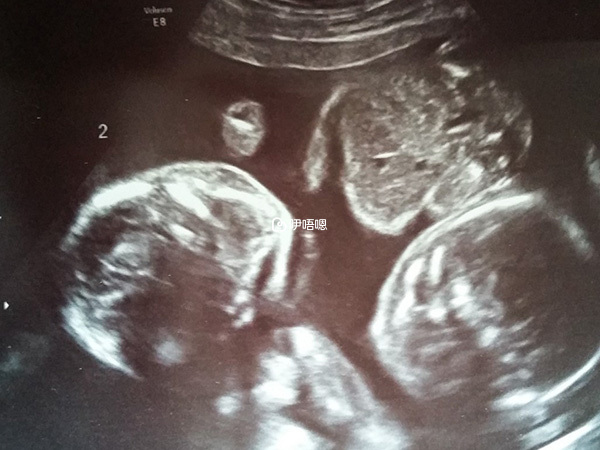

雙胎變一胎

這個男人又不見了,心真的很寒,真的是指望不到!我想我一個人可以照顧好寶寶。所以決定三個月以後離婚回成都,可惜上天就是那麼好玩。8月15日第一次看見寶寶,宮內可見兩個孕囊,HCG6000多,黃體190,不用打針吃藥,2周以後看胎心胎芽!我一個人在醫院外面坐了很久,我要減胎嗎?兩個寶寶我真的照顧得過來嗎?兩個我沒有那個自信,所以為了寶寶我妥協了,給他打了電話,他決定改變自己,迴歸家庭!8月29日第七週了,小寶沒有胎心胎芽!大寶已經可以看到了。

9月12日,第九周小寶被吸收了,大寶一個人佔據媽媽的子宮!寶媽提前拿到媽媽手冊。10月3日第12周。唐篩開始,主要看頸部透明帶的厚度!小傢伙已經成形了,檢查時候還動來動去,跟媽媽一樣覺得不舒服吧!檢查合格!最難熬的三個月寶媽輕鬆度過,沒有孕吐,只是不能餓!到處走、沒有忌諱的,自己煮飯吃、自己買菜、地板自己清潔!